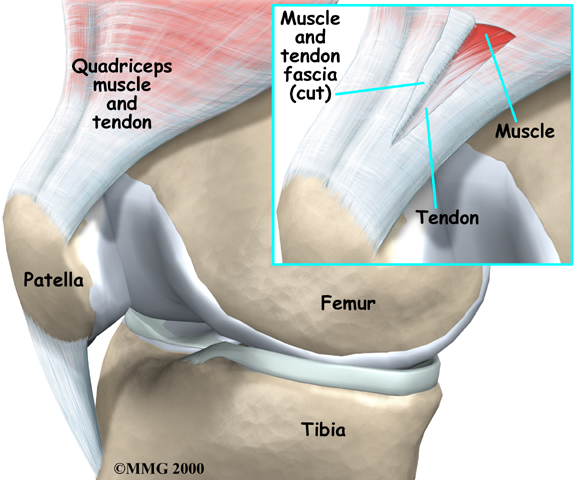

Tendons connect muscle to bone. A tendon is made of material called collagen. Collagen is a key building block of the body. Collagen is considered a connective tissue because it forms tough strands that are like the strands of a nylon rope. Like the strands in a rope, the strands of collagen line up. The more strands, and the better they line up, the stronger they are. The tendon is wrapped in a thin, slippery covering called the tendon sheath. The tendon sheath allows the tendon to slide easily against the tissues around it.

Many parts of the tendon can be injured. Tendon problems can involve the area where the tendon attaches to the bone, the tissue that surrounds the tendon (the tendon sheath), or the main tissues of the tendon. Doctors use different terms to refer to injuries of different parts of the tendon.

Patellar and Quadriceps Tendonitis

Problems in the:

Tendons of the Knee

occur mostly in people whose exercise involves running or jumping. Patellar tendonitis is also called jumper's knee.

Often, the muscles or other tissues of the joints become tight, misaligned, or weak around the area of tendon injury. Some of the pain and swelling of tendonitis may actually be in the surrounding tissues.